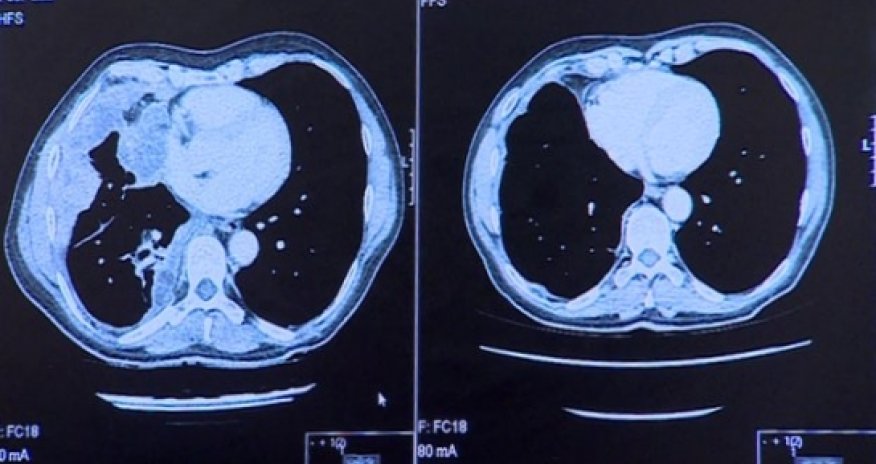

Both treatments, for advanced melanoma, are designed to enable the immune system to recognise and target tumours.The findings were released at the American Society of Clinical Oncology conference in Chicago.The experimental drugs, pembrolizumab and nivolumab, block the biological pathway cancers use to disguise themselves from the immune system.Advanced melanoma - skin cancer which has spread to other organs - has proved very hard to treat.Until a few years ago average survival was around six months.Improved survivalIn a trial of 411 patients evaluating pembrolizumab - 69% of patients survived at least a year.The drug, which used to be known as MK-3475, is also being tested against other tumour types which use the same mechanism to block attack from the immune system.Dr David Chao, consultant oncologist at the Royal Free London NHS Foundation Trust, is conducting trials in both melanoma and lung cancer patients. He said:"Pembrolizumab looks like it has potential to be a paradigm shift for cancer therapy."One of his patients, Warwick Steele, aged 64, has been receiving infusions of pembrolizumab every three weeks since October.Before the treatment started he could barely walk because the melanoma had spread to one of his lungs and he found it hard to breathe."I got tired simply standing up and was literally too exhausted to shave. But now I feel back to normal and can do gardening and go shopping".Scans of his lungs - shown above - reveal that after just three infusions, the drug appears to have completely cleared the cancer from his lung.Combination therapyThe other drug, nivolumab, was tested in combination with an existing licensed immunotherapy, ipilimumab.In a trial of 53 patients, survival was 85% after one year, and 79% after two years.John Wagstaff, Prof of medical oncology at Swansea College of Medicine is part of a larger trial of these two drugs.He said: "I am convinced that this is a breakthrough in treating melanoma."The trial is still "blinded" so we don't know what treatments the patients are getting, but we have seen some spectacular responses."Professor Peter Johnson, Cancer Research UK's chief clinician, said: "It's exciting to see the range of new treatments that are emerging for people with advanced melanoma."But doctors are urging caution. The results which have been published are of Phase I, early stage trials.Much larger Phase III trials are underway involving many UK hospitals.Only when they report, in about a year's time, can clinicians be sure what the likely benefits will be.Like all drugs, the experimental treatments have side effects. Warwick Steele said he experienced night sweats and even had two brief blackouts when on the new drug.But he said it was well worth it, and doctors were now treating these symptoms.(BBC)Bakudaily.az